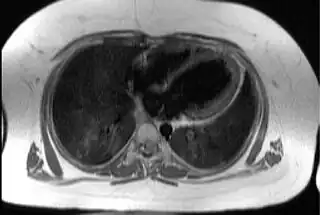

![]() Imagen transaxial del tórax a nivel del corazón, ilustrando la típica capa de tejido adiposo subcutáneo y epicárdico (en blanco) en un paciente con este síndrome. | ||